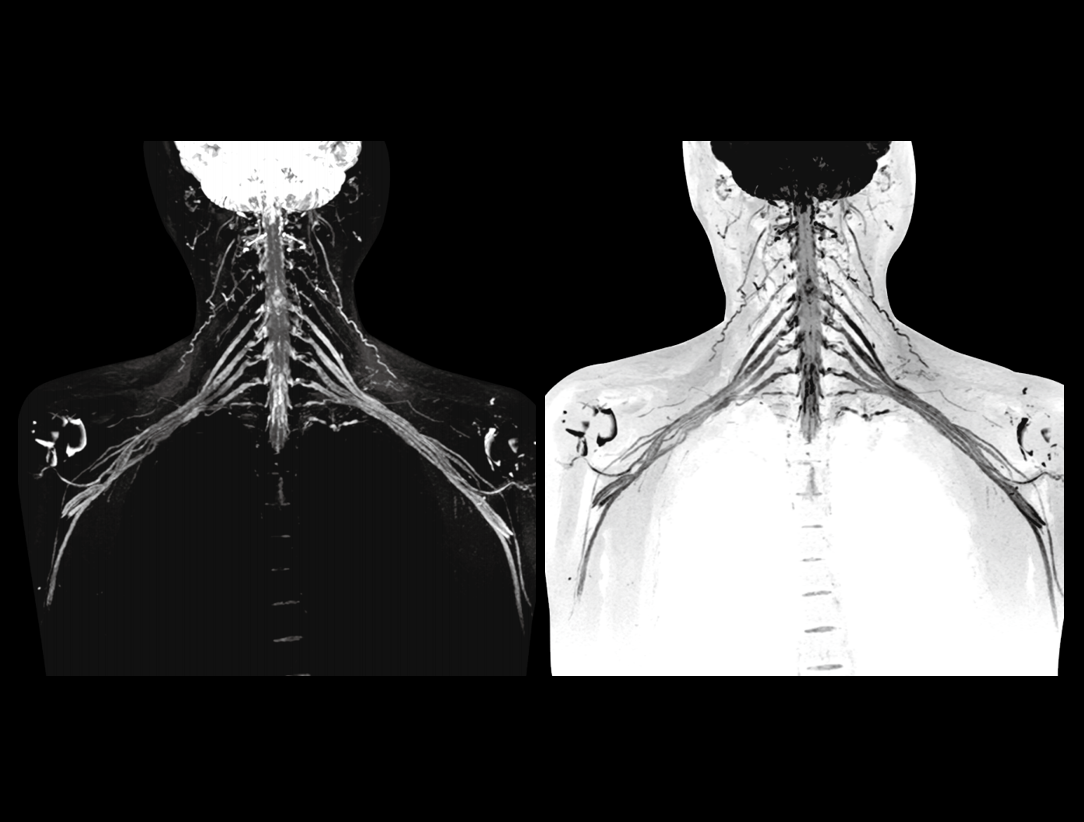

강력한 3.0T 마그넷은 170cm의 짧은 자석 디자인을 사용하여 자기장의 높은 균일성을 보장하여 대형 FOV에서 빠른 영상 촬영 및 우수한 지방 포화(fat saturation) 효과와 뛰어난 오프-센터(off-center) 영상을 제공하는 견고한 기반을 제공합니다.